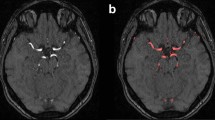

Z-scores evaluation

Figure 5 shows a maximum intensity projection visualization of an individual artery segmentation of a dataset not used for the atlas generation with the color-coded absolute z-scores. The high z-scores, in red, indicate regions where the individual cerebroarterial system varies the most from the population average. As a healthy subject was used for this experiment, it is expected that there are only a few, potentially noise-related, high z-scores. This experiment shows that z-scores values might be valuable to detect vessel abnormalities.